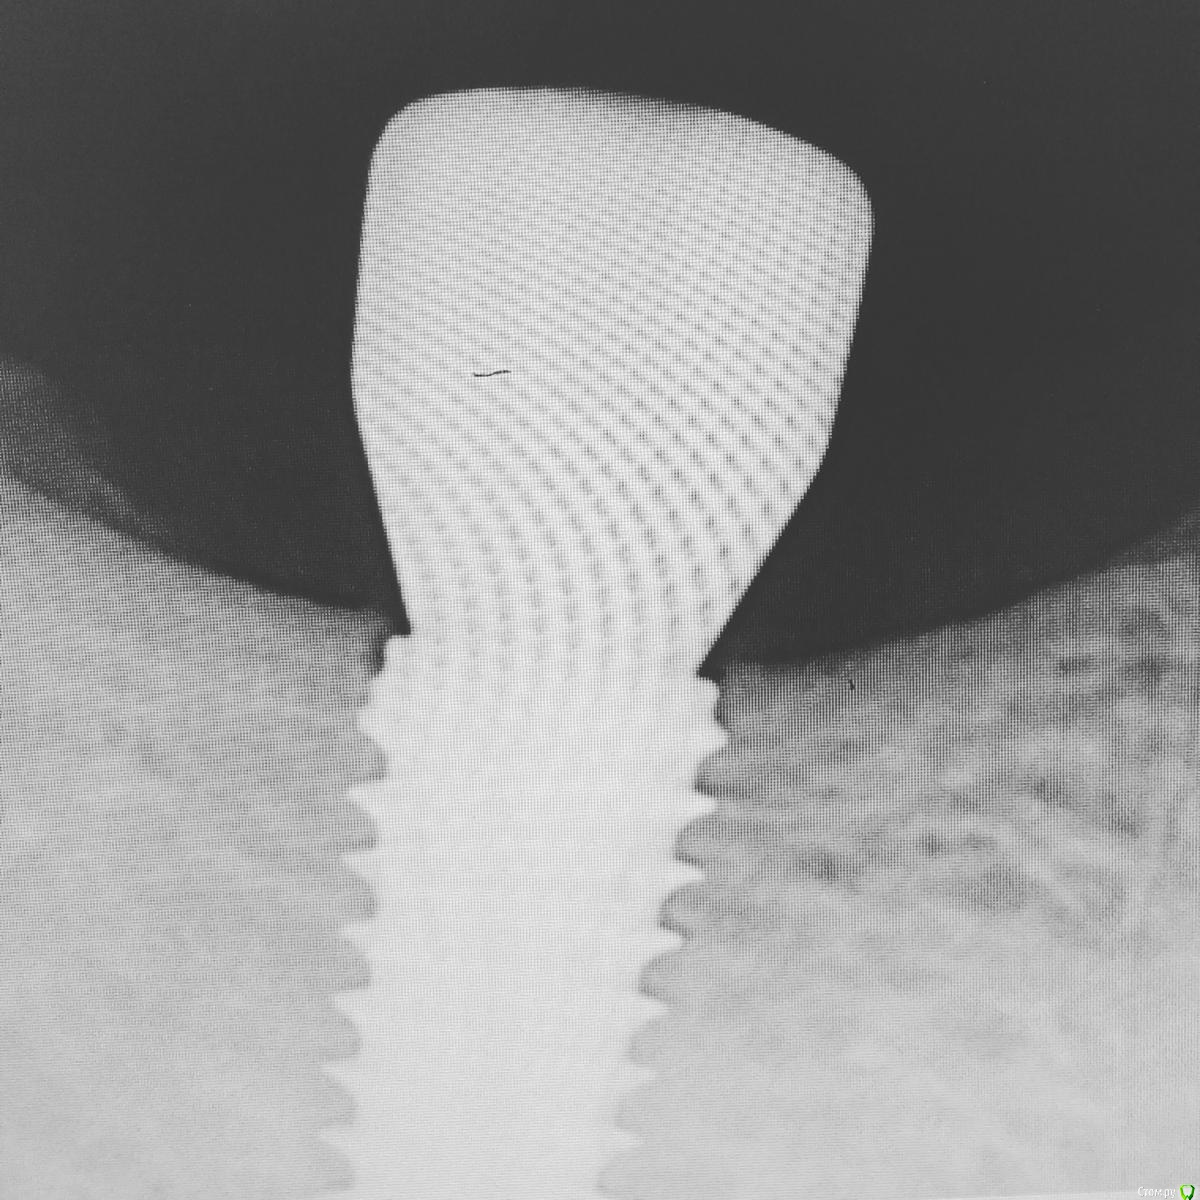

NazranDantist Опубликовано 20 июля, 2016 Поделиться Опубликовано 20 июля, 2016 Фдм дентиум Ссылка на комментарий